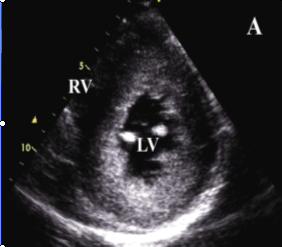

後者是與風濕性主動脈瓣狹窄病理學鑑別要點。先天性主動脈瓣二葉式畸形的占先天性主動脈瓣異常的50%以上。歷經幾十年後才逐漸形成主動脈瓣狹窄,其中約40%伴主動脈瓣關閉不全。上述主動脈瓣狹窄的診斷可根據病史和體徵結合X線心電圖、超聲心動圖及左心導管檢查,一般可作出病因診斷。